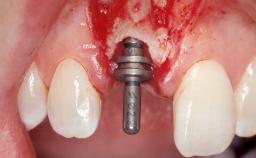

Immediate Flapless Placement of an Implant in a Maxillary Left Central Incisor Site

A 29-year-old female patient presented for treatment to replace the upper left central incisor tooth with an implant- supported restoration. The tooth had been intermittently symptomatic for the previous 12 months. The tooth had originally suffered trauma about 15 years previously. Several endodontic treatments had been performed, including an apicectomy procedure to retain the tooth. The patient was healthy and a non-smoker. She had reasonable expectations in regard to esthetic outcomes and the risk of marginal tissue recession following treatment. At medium smile, the gingival margins of the upper teeth were visible, with a display of 3 to 4 mm of the gingival margins. Gingival recession of tooth 21 and a discrepancy in the gingival levels between teeth 11 and 21 was observable during normal speech and smile.

Type of Implants One-Piece

Attachment One-Piece

Placement Protocol Immediate implant placement

Tooth Site Maxillary incisor or canine